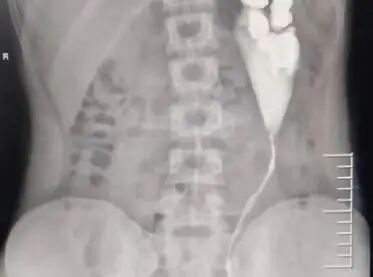

患者术后影像学检查

术后复查结果显示,小元左侧肾积水明显减轻,受损的肾功能也逐渐恢复。由于手术创伤较小,他恢复顺利,术后第4天便康复出院了。